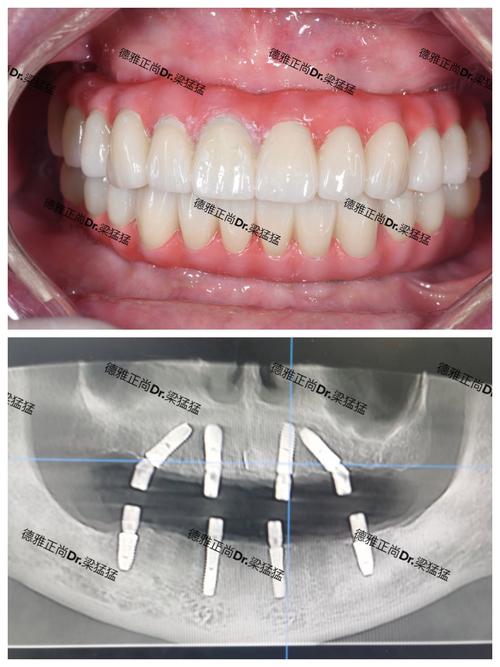

- 案例沟通:要求查看医生过往类似案例,了解术后效果与患者反馈,尤其是全口、半口等复杂种植案例。